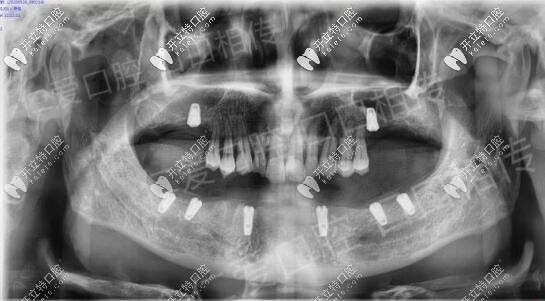

年前來(lái)到醫(yī)院口腔咨詢種植牙,上頜先種2顆,下頜把松牙拔除,等待恢復(fù)后下頜做all-on-6,種6顆,恢復(fù)半口。

疫情前把該拔的殘根松動(dòng)牙拔除恢復(fù)到現(xiàn)在,主要設(shè)計(jì)的ALL-ON-N種6恢復(fù)下半口,今天已成功種植8顆植體

術(shù)后裝上過(guò)渡性樹脂義齒,等待種植體與骨質(zhì)結(jié)合較好之時(shí)再進(jìn)行長(zhǎng)久性牙齒佩戴,老爸現(xiàn)在咀嚼穩(wěn)定健康,重啟生活質(zhì)量,他高興,我也感覺(jué)欣慰。